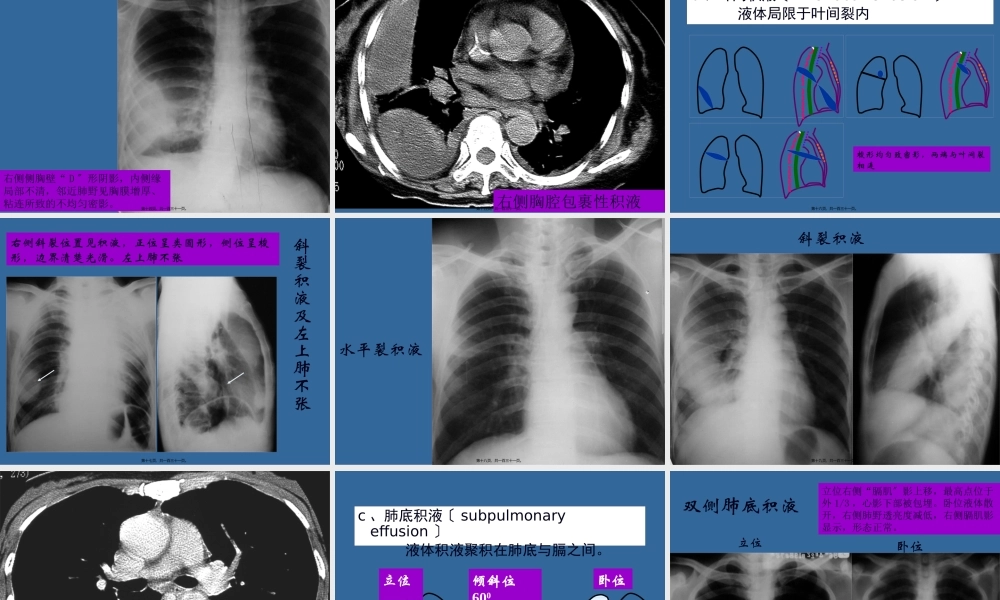

呼吸系统〔二〕伍尧泮中山大学肿瘤医院2022313第一页,共一百三十一页。呼吸系统〔二〕第二页,共一百三十一页。根本病变影像学征象第三页,共一百三十一页。〔一〕胸腔积液〔pleuraleffusion)分类:游离性胸腔积液包裹性胸腔积液第四页,共一百三十一页。•少量积液:最先位于后肋膈角,但站立位胸片难以发现;液量达250ml时,站立位胸片显示侧肋膈角变钝或消失;液量进一步增加可遮盖膈面,上缘在第4肋前端以下,呈外高内低的弧形影;•中量积液:上缘在第2肋前端以下、第4肋前端以上,上缘呈外高内低的弧形影;•大量积液:上缘在第2肋前端以上,患侧肺野均匀致密有时仅见肺尖部透明;患侧肋间隙增宽、膈肌下降、纵隔向健侧移位。第五页,共一百三十一页。第六页,共一百三十一页。第七页,共一百三十一页。双侧少量胸水双侧外侧肋膈角变钝,上缘呈弧形向外上。第八页,共一百三十一页。左侧中等量胸腔积液左侧中下肺野均匀致密影,上缘弧形向外上,第九页,共一百三十一页。一侧大量胸腔积液〔左侧〕左侧肺野均匀致密,气管、心影右移第十页,共一百三十一页。CT示胸腔积液第十一页,共一百三十一页。•包裹性胸腔积液:胸膜炎后脏层和壁层胸膜粘连使液体聚集于胸腔某一部;•叶间积液:液体局限于水平裂或斜裂内,位于斜裂者正位胸片难以诊断;•肺底积液:积液位于肺底与膈间胸膜腔,膈影升高。第十二页,共一百三十一页。a、包裹性积液〔encapsulatedeffusion〕炎症致脏层、壁层胸膜粘连,液体局限,好发生于侧后胸壁。钝角边界清,密度均匀第十三页,共一百三十一页。包裹性积液右侧侧胸壁“D〞形阴影,内侧缘局部不清,邻近肺野见胸膜增厚、粘连所致的不均匀密影。第十四页,共一百三十一页。右侧胸腔包裹性积液第十五页,共一百三十一页。b、叶间积液〔interlobareffusion〕液体局限于叶间裂内梭形均匀致密影,两端与叶间裂相连第十六页,共一百三十一页。斜裂积液及左上肺不张右侧斜裂位置见积液,正位呈类圆形,侧位呈梭形,边界清楚光滑。左上肺不张第十七页,共一百三十一页。水平裂积液第十八页,共一百三十一页。斜裂积液第十九页,共一百三十一页。右侧斜裂间积液第二十页,共一百三十一页。c、肺底积液〔subpulmonaryeffusion〕液体积液聚积在肺底与膈之间。立位卧位倾斜位600肝下界位置正常变深、变锐最高点在外1/3第二十一页,共一百三十一页。双侧肺底积液卧位立位立位右侧“膈肌〞影上移,最高点位于外1/3,心影下部被包埋。...

二年级数学下册其中检测卷二年级数学下册其中检测卷附答案#期中测试卷.pdf

10.00金币

0下载

二年级数学下册期末质检卷(苏教版)二年级数学下册期末质检卷(苏教版)#期末复习 #期末测试卷 #二年级数学 #二年级数学下册#关注我持续更新小学知识.pdf

二年级数学下册期末混合运算专项练习二年级数学下册期末混合运算专项练习#二年级#二年级数学下册#关注我持续更新小学知识 #知识分享 #家长收藏孩子受益.pdf

1下载

二年级数学下册年月日三类周期问题解题方法二年级数学下册年月日三类周期问题解题方法#二年级#二年级数学下册#知识分享 #关注我持续更新小学知识 #家长收藏孩子受益.pdf